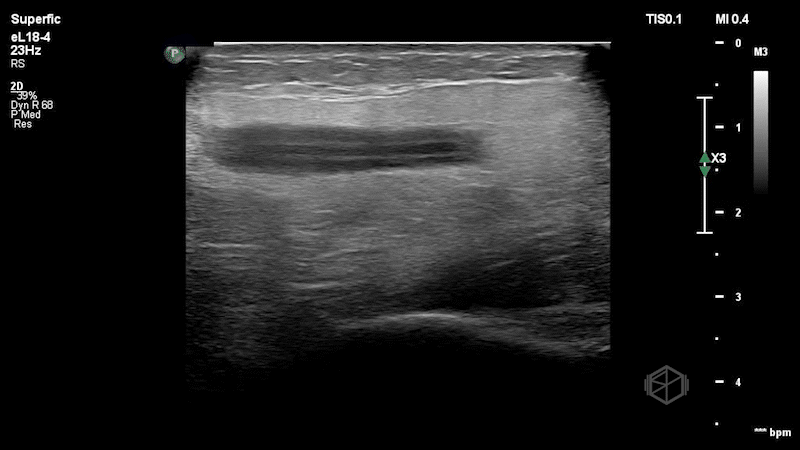

Dr. Simon very carefully performed an ocular ultrasound:

Upon seeing this he immediately terminated the ultrasound having made the diagnosis. With multiple differentials to consider this ultrasound has some great findings. The anterior chamber of the eye demonstrates layering fluid. The vitreous body is completely heterogenous instead of anechoic. There is no guitar pick sign or anechoic material posterior the eye that would indicate a retrobulbar hematoma. The patient was evaluated by ophthalmology that confirmed his diagnosis and the patient was transferred for ophthalmologic surgery.

Diagnosis: Traumatic globe rupture with significant vitreous hemorrhage and a hyphema

• A hyphema appears as a settled echogenic blood within the aqueous of the anterior chamber.

• This patient has a significant vitreous hemorrhage/intraocular hematoma as noted by the entire vitreous body filled with echogenic material.

• The globe rupture is suggested by the decreased size of the globe, indicating loss of pressure or vitreous.